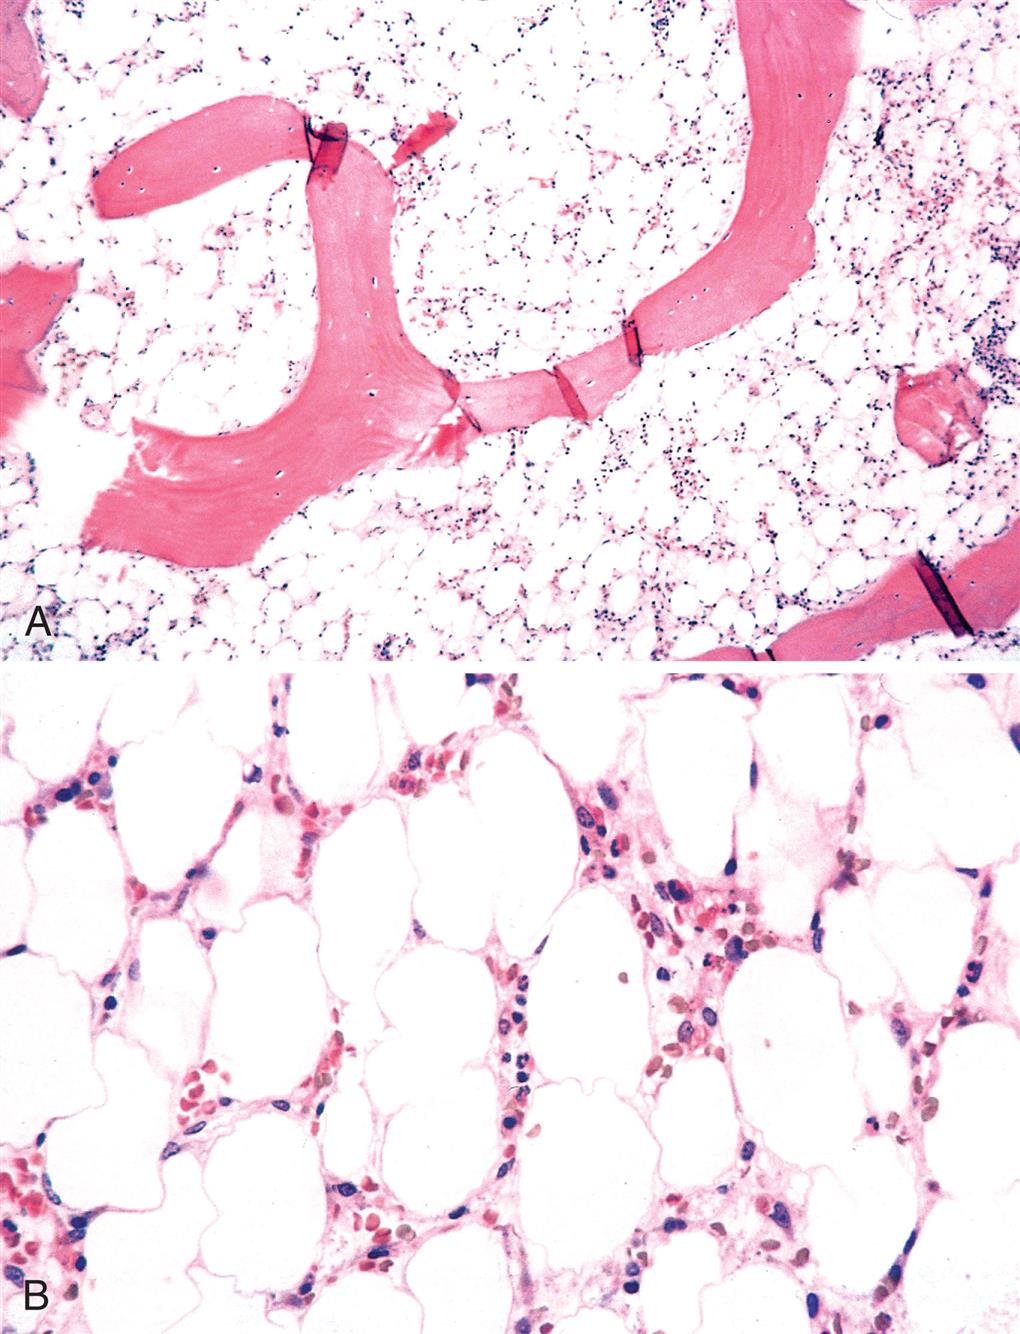

Aplastic anemia (AA) is a hematopoietic failure of the bone marrow leading to a reduction in the effective production of mature blood cells and resulting in peripheral pancytopenia (anemia, neutropenia, and thrombocytopenia), which is a reduction or absence of all three blood cell types. (Fig. 29.7) The incidence of AA in the United States is low; however, the incidence in developing countries is higher related to greater exposure to certain chemicals known to cause AA. The incidence is bimodal, with one peak occurring between 15 and 25 years of age and a second peak occurring in individuals older than age 60. AA is equally distributed between genders.

The characteristic lesion of AA is a hypocellular bone marrow that has been replaced with fat. Although the pathogenesis is not fully defined, AA results from loss of hematopoietic stem cells (HSCs) or their progenitors at various stages of differentiation. Two etiologies and mechanisms are observed: an immune-mediated destruction of bone marrow progenitor cells (idiopathic AA) and an intrinsic abnormality of stem cells (secondary AA).

AA is suspected if levels of circulating erythrocytes, leukocytes, and platelets are diminished. The diagnosis is confirmed by bone marrow biopsy. The bone marrow usually has reduced cellularity (e.g., less than 25% normal cellularity). The morphology of the few remaining hematopoietic cells is usually normal. Occasionally the erythrocytes are macrocytic, with anisocytosis and poikilocytosis, and may appear immature.